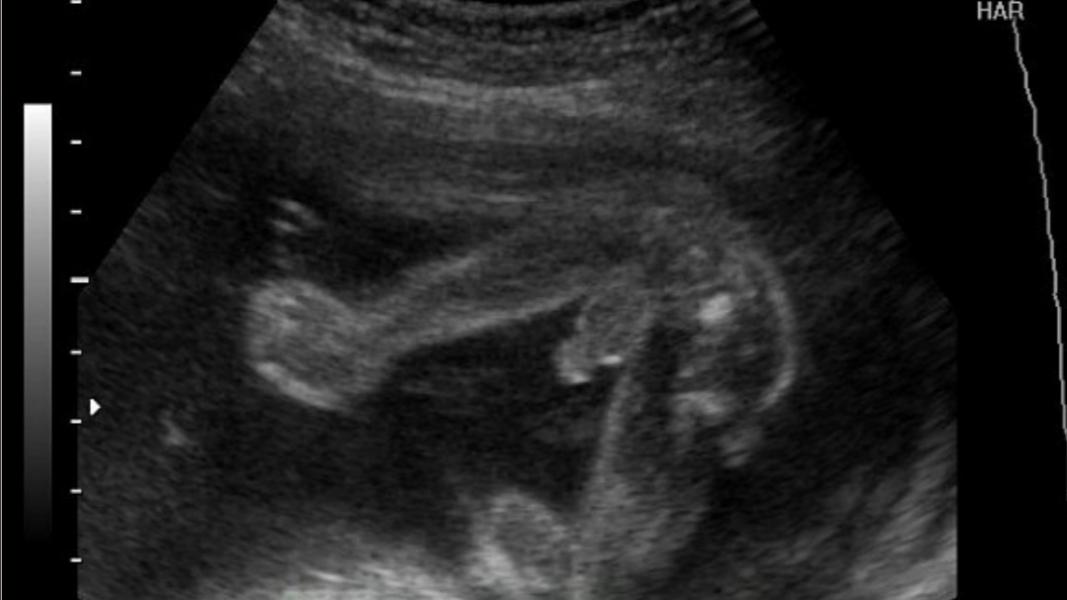

Пришла я на второй скрининг, все как полагается, положила конверт и бумажку, прошу пол сохранить в секретике. Хотелось на третьем ребенке каких то впечатлений и родне интересно сообщить. Врач смотрит на меня и говорит "ну если увидим", поскольку я далеко не дрыщ. Я без особых надежд, ложусь, а передо мной экран висит. Несколько минут она фиксировала общие параметры, вес итд. Потом ставит датчик резко в другое место и передо мной картинка типа как на фото, только двигается. Озвучивает: длина бедра, почки, пуповина, мочеточники.. и я понимаю, что это явно не девочка😄 Я говорю : это же не пуповина?

п.с. Фото из интернета

Я с первым сыном не сильно парилась и когда сказали, что мальчик даже не удивилась, почему-то была уверенна и ожидаемо🤷🏻♀️в этот раз хотела девочку )) смотрели долго и не показывал ребенок , потом увидела животик и подумала что мальчиковый))) в итоге тоже поймали как на фото, сел на попу и там все 🥚🥕🥚 прям видно между ножек 🤦🏼♀️реально не спутать)) в итоге врач даже проверила кровоток, что это точно орган, а не пуповина 😂😂😂

Вот у меня во вторую беременность так, в16 недель пошла специально пол узнать, говорю напишите на листочке,большой телевизор висит на стене ,я легла врач датчик ставит и тут картина маслом 🤣🤣🤣🤣 точно так как на вашей картинке, смеялись мы конечно долго 🤣 ну хоть мужу сделала сюрприз 😃

У нас было именно так, как вы описали! Мы с мужем поржали, когда врач намазала гель, навела датчик и перед нами точно такая же картина, как на фото! Там, уж и плохо видящий разглядит причендалы 😂👍

Как будто малыша посадили на стеклянный стол и сфоткали снизу

Сидит попой, разведённые ноги и писюн с яйцами посередине

@vladlenka_009 так вот попой как будто к нам сидит ножки растопырил. Посередине мужское всё)